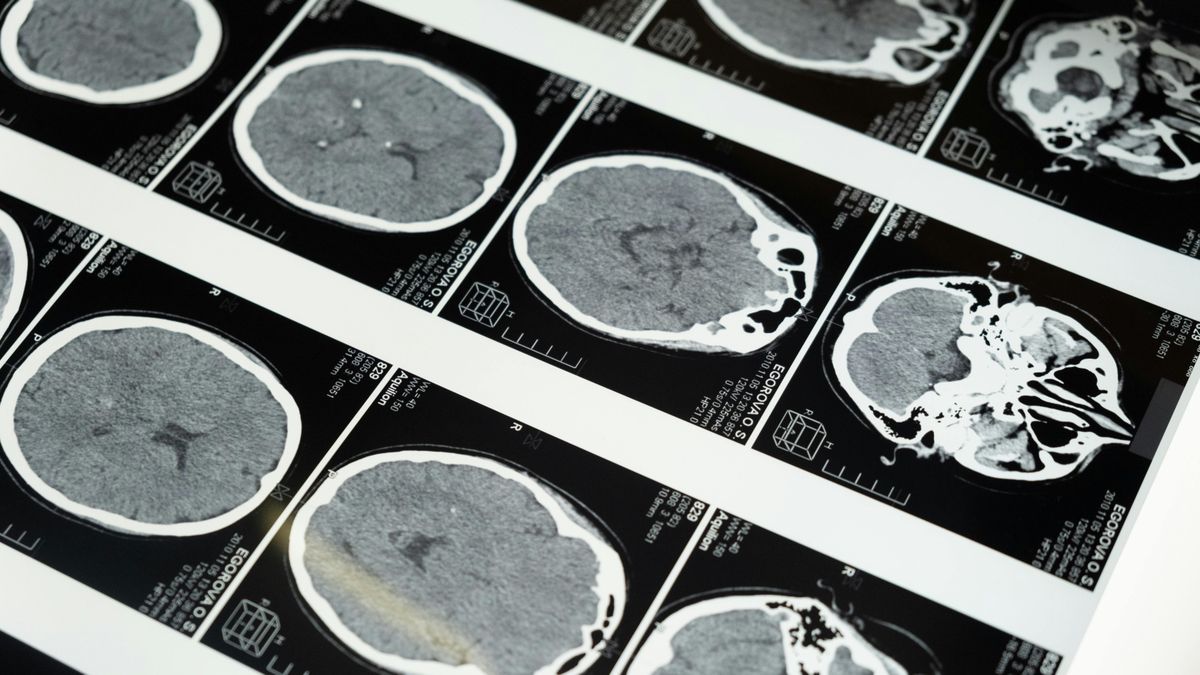

Magyar kutatók rájöttek, miért emlékezünk a szokatlan dolgokra is, annak ellenére, hogy elméletben nem kellene

Az információelmélet alapján az agynak nem lenne érdemes a túl ritka vagy szokatlan élményeket megjegyeznie. Ennek ellenére éppen ezek a meglepő élmények gyakran mély és gazdag nyomot hagynak a memóriában.